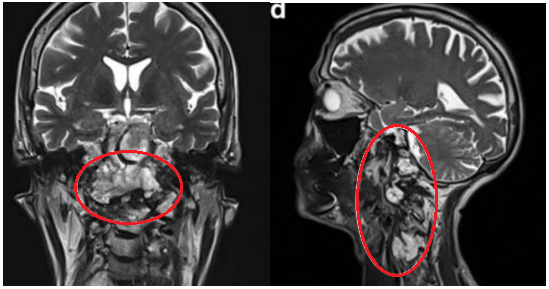

这位年轻女性因颈部疼痛就诊,MRI发现颅颈交界区脊索瘤,伴骨质破坏和硬膜内延伸,累及双侧椎动脉。

术前MRI

手术策略:INC福洛里希教授采用了内镜辅助的前外侧入路,顺利切除肿瘤。术后几天行枕颈融合术确保稳定性。

术后MRI